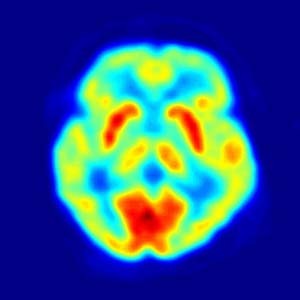

Brain image taken with positron emission tomography (PET)

The UK research community will soon have access to world-class medical imaging facilities in London with the signing of an agreement today between an alliance of leading London-based universities, the Medical Research Council (MRC) and the pharmaceutical company GlaxoSmithKline (GSK). In a unique partnership, the MRC, UCL, Imperial College London and King's College London become equal shareholders in a newly created joint venture that assumes responsibility for the facilities and operations at GSK's Clinical Imaging Centre (CIC). The £47m centre on Imperial College London's Hammersmith Hospital campus has carried out GSK-dedicated research in close collaboration with academic researchers since it opened in 2007. Under the new arrangements, the research and technical expertise of the four partners will help to drive the centre into new areas and applications of imaging. "This new joint venture creates a framework for collaborative science across academia, pharmaceutical and biotechnology organisations. The three universities, with the MRC, will work in cooperation with GSK to establish the facility as the UK's leading clinical imaging centre which will play a vital role in accelerating the translation of biomedical research into healthcare and economic benefits," said Dr Jim Hagan, CEO of Global Medical Excellence Cluster (GMEC). GMEC - a public private partnership dedicated to building the UK's research biomedical research capabilities and enhancing the UK's competitive position - worked closely with the three academic partners and the MRC to develop and deliver this new operating model.